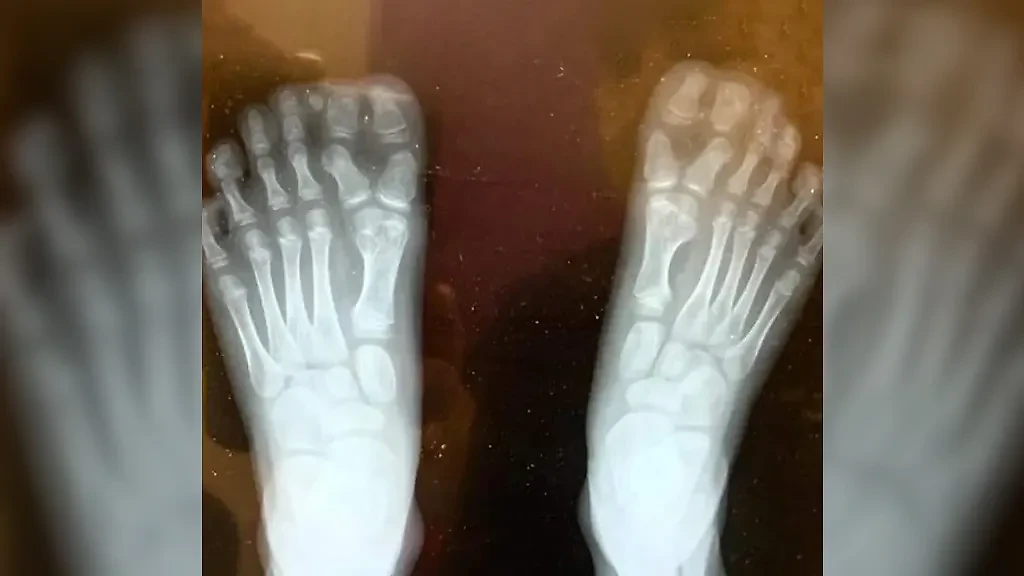

"Рентгенограмма стоп моего сына", — jsams18.

Фото © Reddit / jsams18